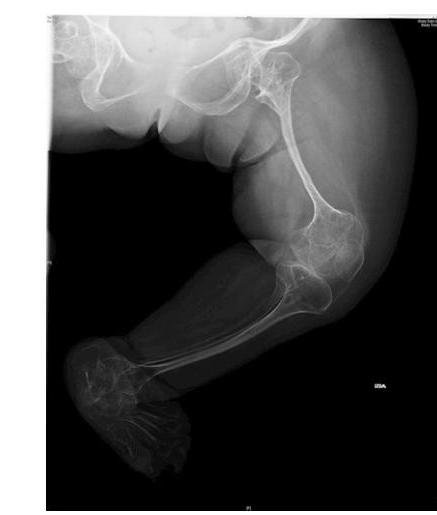

# OSTEOGÉNESIS IMPERFECTA ## DEFINICIÓN Es un grupo de **enfermedades genéticas hereditarias** del **tejido conectivo** caracterizadas por la presencia de **fragilidad ósea** y **fracturas**. Existen 6 tipos de osteogénesis imperfecta (I-VI), siendo el **tipo II** la forma **más severa** y generalmente **letal**. ## ETIOLOGÍA Se produce debido a mutaciones en los genes que codifican la **COLÁGENA TIPO 1**: - **COL1A1** (cromosoma 17) - **COL1A2** (cromosoma 7) La herencia más frecuente es la **AUTOSÓMICA DOMINANTE**. ## EPIDEMIOLOGÍA ## FACTORES DE RIESGO - **EDAD PATERNA AVANZADA** - **HISTORIA FAMILIAR** ## CLÍNICA Puede ser confundida con **fracturas múltiples** por **maltrato infantil**. Es característica la presencia de **ESCLERÓTICAS AZULES**. - **Fracturas** después de **traumatismos de baja energía**, en ausencia de otros factores. - **Retraso en el desarrollo psicomotor**. - **Talla baja**, **deformidad de huesos largos** y **columna vertebral**. - **Dentinogénesis imperfecta**, **dientes opalescentes**. - **Hipoacusia**. - **Hiperlaxitud articular**. # DIAGNÓSTICO **GOLD ESTÁNDAR**: **HISTORIA CLÍNICA** y **EXAMEN FÍSICO**. **USG**. Para realizar **diagnóstico INTRAUTERINO**. **ESTUDIO MOLECULAR**. Analiza el **COLÁGENO TIPO 1** y los genes implicados **COL1A1** y **COL1A2**. **RADIOGRAFÍA**. Se puede observar **osteopenia**, **fracturas** y **arqueamiento de huesos largos**. **ANÁLISIS DE SANGRE**. Los niveles de **VITAMINA D**, **FÓSFORO**, **CALCIO** y **FOSFATASA ALCALINA** se encuentran normales.  ## TRATAMIENTO Primera elección: **PREVENCIÓN DE FRACTURAS** con **USO DE COLCHONES ESPECIALES** y **EVITAR DEPORTES**. - **Analgésicos**: para manejo del **dolor** en las **fracturas**. - **Cirugía**: para el manejo de la **escoliosis** y **cifosis**. - **Bifosfonatos**: reducen el **dolor** y el número de **fracturas**. - **Programas de ejercicio**: Se recomienda la **natación**. ## PRONÓSTICO - Dependerá del tipo de osteogénesis imperfecta, siendo el **TIPO II** la **más severa**. - Pueden presentar desde **muerte perinatal** hasta **ausencia de síntomas**.